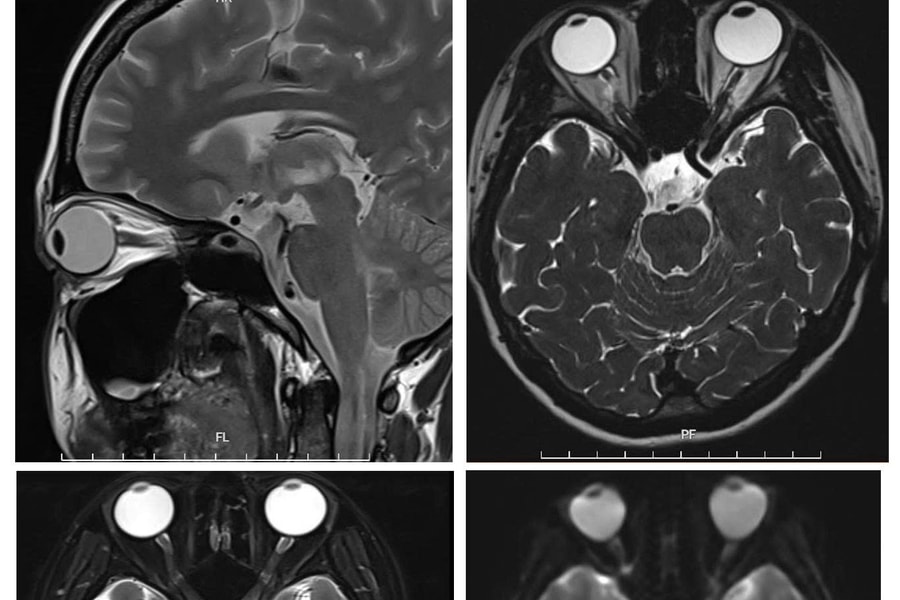

“Giải thoát” nữ bệnh nhân khỏi bệnh rối loạn phổ viêm tủy thị thần kinh thể hiếm gặp

Bệnh viện Đa khoa tỉnh Phú Thọ thông tin về việc đơn vị vừa điều trị thành công cho một trường hợp rối loạn phổ viêm tủy thị thần kinh thể hiếm gặp.